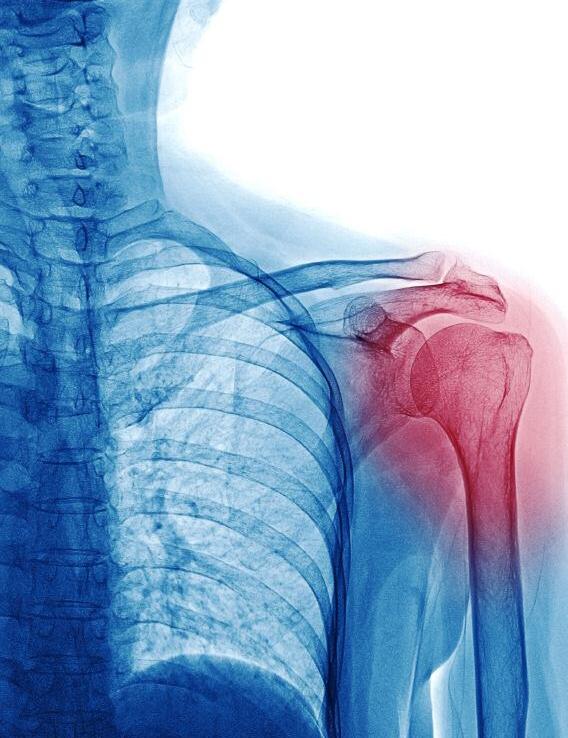

ROME REVISION SHOULDER ARTHROPLASTY

Intervista a Francesco Franceschi di Gianandrea Sapio Professore associato di Ortopedia UniCamillus; primario di Ortopedia Ospedale San Pietro Fatebenefratelli di Roma

Quello che abbiamo organizzato insieme al professor Cosimo Tudisco, titolare della cattedra di Ortopedia e Traumatologia della nostra unive evento che attuale e cio degli impian

Le protesi di c e d u r e c h i sono cresciu mero espone n e g l i u l t i m i anni proprio miglioramen

tecniche chi per l’aumen media della mondiale

l’arto superiore al di sopra della spalla Soprattutto negli anziani subiscono una degenerazione progressiva fino a riassorbirsi completamente e non far muovere piu l’articolazione In questi casi si impianta la p r o t e s i c o s i d d e t t a “ i n v e r s a ” c h e i n v e r t e l’anatomia dell’articolazione. Dove c’era una convessità questa viene sostituita da una concavità ed al posto della concavità della superficie scapolare, la glenoide, s’inserisce una componente convessa Questo disegno biomeccanico permette di mantenere fisse le componenti articolari e fa muovere il braccio in alto anche senza l’aiuto dei tendini